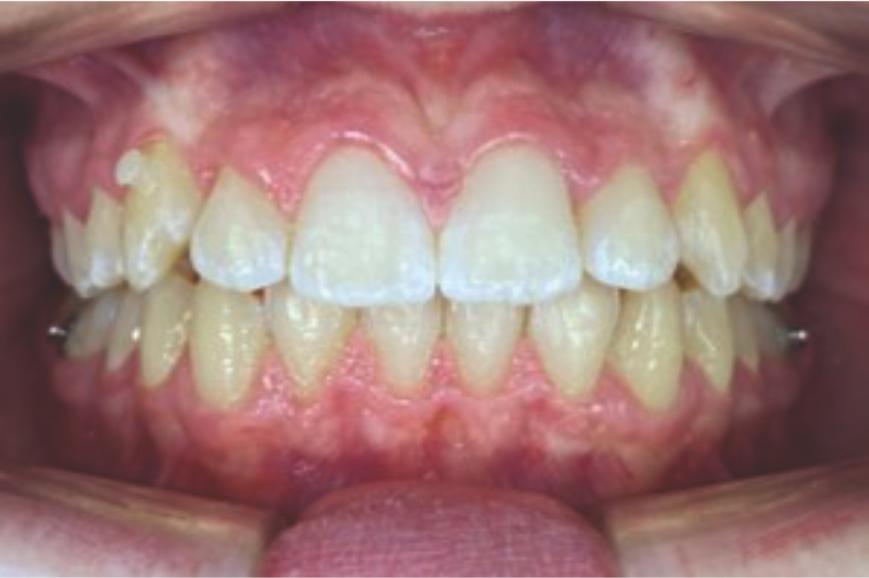

Chief complaint: We present the case of a 12-year-old female patient who came for an orthodontic evaluation, motivated by a family history of treatment. Clinical and radiographic analysis revealed a skeletal Class II malocclusion with molar and canine relationships also in Class II, moderate crowding in both arches, a deviation of the dental midline, and ectopic eruption of tooth 13. No functional issues with breathing or swallowing were observed, and oral health was generally good. A slight mandibular retrusion was noted in the soft tissue profile. A treatment plan was proposed using the Angel Aligner Pro system, aiming to correct dental misalignments and improve facial harmony through a minimally invasive, growth-adapted approach.

Clinical examination and diagnosis

- Woman ; 12/3 years

- Skeletal Class II

- Molar and canine Class II

- Upper and lower dentoalveolar compression

- Increased overjet and overbite

- Upper midline deviated 0,5 mm to the right

- Moderate upper and lower crowding